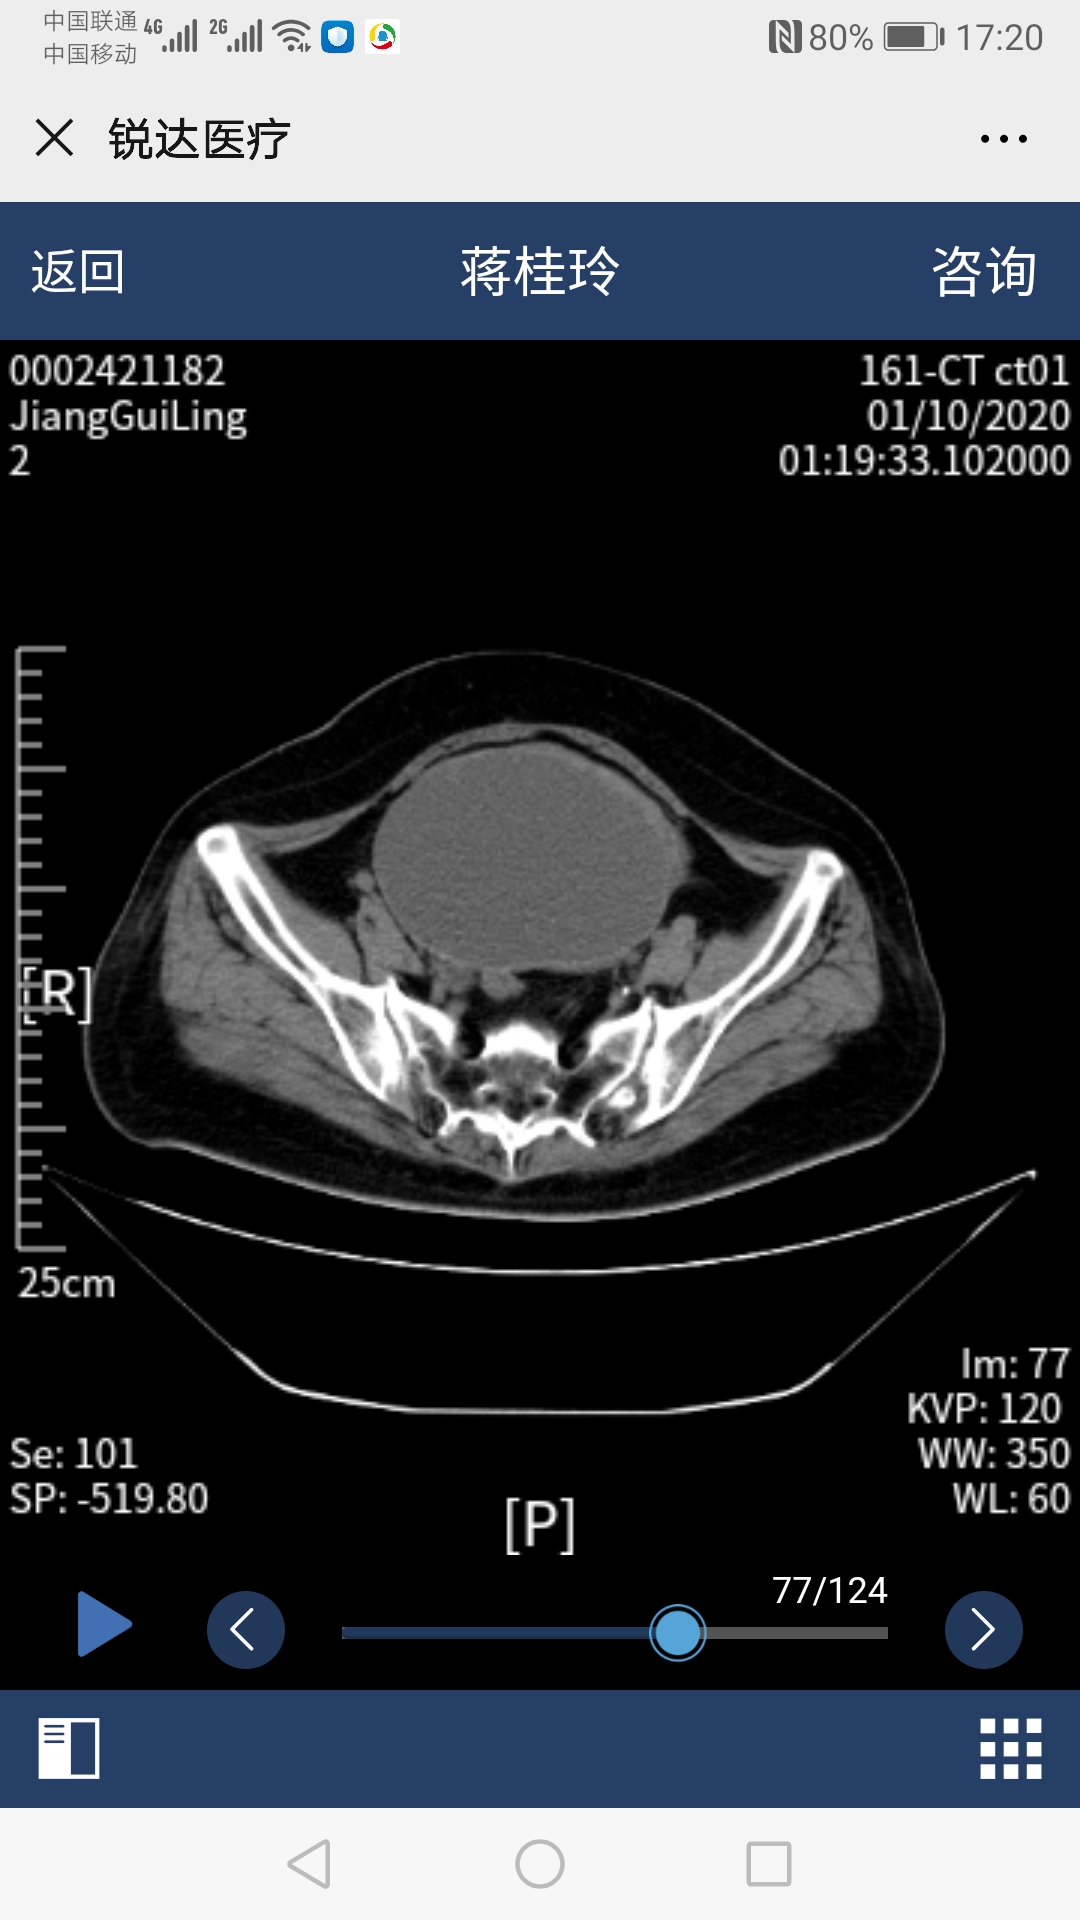

54岁的蒋阿姨最近常常觉得腹部胀痛,没有食欲,排便困难。肚子上出现一个包块,且越来越大。在当地医院就诊发现腹部有一个巨大的囊性肿物(12cm*8cm*12.6cm),但却同时检查出了患有先天性心脏病--房间隔缺损,并且已经出现了右心衰竭和明显肺动脉高压症状,加上既往冠心病、糖尿病、肾结石等多种疾病,医生在询问病史、完善检查之后说道:"你这手术风险太大,还是到别的医院试一试吧,我们这里不敢做"。蒋阿姨先后在省内多家大医院奔波求医,有的建议外科手术治疗腹部肿块,但因有房间隔缺损等多种疾病,风险较大;有的建议先做房间隔缺损手术,但术后需抗栓治疗6个月,期间不方便行腹部肿块手术,那就要继续忍受6个月的痛苦;总之,没有找到合适的方案。 正在蒋阿姨痛苦万分的时候,她听说哈医大四院心内科*巍杨**主任技术高超,医院整体实力雄厚,可能有更好的方案。蒋阿姨一家慕名来到了心内七病房,看着在病床上挣扎的蒋阿姨,杨主任急患者之所急,积极策划全院会诊,在院领导及医务科的协调下,邀请心内科、妇科、普外科、消化科、肿瘤科、心脏超声科、彩超室参与患者病情讨论,专家们建议患者先*房行**间隔缺损封堵术,再进行腹部囊肿穿刺术。手术于会诊后立即实行,*巍杨**主任、张明宇主任及心内科彩超室薛莉主任采用微创方法实施房间隔缺损封堵术,术后一周由彩超室董晓秋主任和刘瑞松医师为她做了腹部巨大囊性肿物穿刺引流术,3天共引流出1000毫升血性液体,后成功撤出引流管,蒋阿姨腹部胀痛等不良感觉消失。在心内七病房全体医护人员的悉心照料,蒋阿姨术后恢复良好,没有出现任何并发症及不良反应,顺利出院。